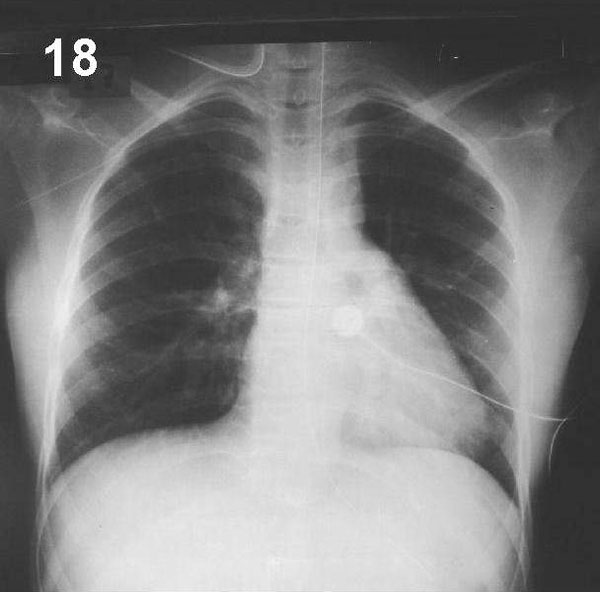

PLACA 18

La opacidad generada por una atelectasia tiene una situación y forma característica según los lóbulos o segmentos colapsados. El signo de la silueta puede estar presente y puede observarse broncograma aéreo, siempre que la atelectasia no se deba a una obstrucción bronquial con reabsorción del aire hacia distal. En ocasiones, la atelectasia puede detectarse por la sobreinflación compensatoria del parénquima vecino.